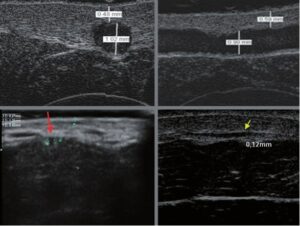

La ecografía Doppler permite obtener imágenes de grandes vasos y perforantes que suelen estar situados en las capas más profundas del tejido subcutáneo (fig. 1). Desgraciadamente, la ecografía convencional no es capaz de obtener imágenes de vasos más pequeños. Para visualizar los vasos más pequeños situados cerca de la superficie de la epidermis y en la capa superior del tejido subcutáneo, se utiliza el HFU (fig. 1). Gracias al uso de transductores con frecuencias superiores a 20 MHz, se obtiene una imagen ecográfica de alta resolución en la que podemos diferenciar estructuras menores de 0,1 mm. Sin embargo, cuanto mayor es la resolución, menor es la penetración del haz de ultrasonidos en las capas de la piel. Por lo tanto, dependiendo del transductor y del aparato, es posible penetrar en la piel hasta una profundidad de 20-30 mm como máximo. Tal penetración, junto con la alta resolución de la imagen, permite la evaluación incluso de vasos sanguíneos muy pequeños (fig. 2). Durante el examen con el uso de transductores de alta frecuencia, se puede evaluar con precisión el curso y la ubicación de los pequeños vasos en la piel. Esto es particularmente relevante para la selección del método de cierre del vaso y la planificación del procedimiento ya que, en la práctica, la superficie de la piel muestra muy a menudo únicamente un pequeño número de vasos o un ligero fragmento de un vaso; solo tras el examen por ecografía podemos determinar su número y curso reales. Para un cierre eficaz del vaso, es necesario hacerlo en toda su longitud. No debe limitarse al fragmento visto «a simple vista» en la superficie de la piel, ya que el cierre del fragmento causará su rápida recanalización(7). Con frecuencia, el vaso visible en la superficie de la piel cambia su curso, se vuelve más tortuoso y se desplaza a las capas más profundas de la piel(8). Por lo tanto, el curso de la vena y las perforantes deben conocerse y determinarse bien antes del procedimiento. El HFU también permite obtener imágenes de las perforantes entre pequeños vasos. Además, aparte de la evaluación del curso y la anatomía, la imagen ecográfica, gracias al software de ultrasonidos, también permite determinar los parámetros básicos como el diámetro del vaso, el grosor de su pared, la profundidad en la piel así como la presencia o ausencia de perfusión en el interior del vaso(6) (fig. 3). Gracias al transductor electrónico multielemento con la frecuencia de 40 MHz introducido en el mercado por Ultrasonix, también es posible visualizar la perfusión en los vasos en el modo Doppler color (fig. 4).

Los tratamientos con láser consistentes en un cierre transcutáneo de los vasos son cada vez más populares. La esencia de estos tratamientos consiste en enviar un haz de luz sobre el vaso, que es absorbido por la hemoglobina contenida en los eritrocitos y transformada en energía térmica. Esto provoca el calentamiento de la pared del vaso y su coagulación. Mientras que en las telangiectasias leves el efecto se obtiene de forma inmediata, en las venas reticulares el cierre se produce varias semanas después del procedimiento(9). La eficacia de la terapia depende de la selección adecuada de los parámetros del tratamiento. La determinación de la ubicación de los vasos en las capas de la piel y sus diámetros tienen gran importancia. Estos dos parámetros pueden especificarse con precisión en el HFU. En función de los hallazgos de la ecografía, se selecciona el tipo de láser, lo que conlleva la selección de la longitud de onda, la anchura del pulso, el diámetro del spotsize y la energía del pulso(7). En la terapia láser, el HFU también es útil como método para monitorizar la corrección del tratamiento y su eficacia. Durante el procedimiento, la ecografía puede ayudar a garantizar que la energía del láser llega al vaso; su diámetro debería disminuir de inmediato (fig. 5). Cuando no se detecta tal efecto, deben verificarse los parámetros del tratamiento. Además, debe comprobarse si el cabezal del láser se aplica adecuadamente a la piel. El HFU también se utiliza para evaluar la eficacia de los procedimientos realizados. Los parámetros útiles en dicha evaluación son: presencia o falta de perfusión en el vaso, presencia o ausencia de un trombo en la luz del vaso, diámetro del vaso y grosor de su pared.